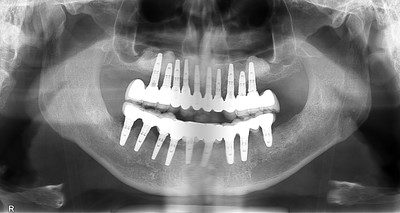

Implant treatment completed in the Phillipines. Twenty implants were placed; standard best practice for this type of case is to place only ten implants. At the time this x-ray was taken, one of the lower implants had failed and already been removed. All remaining implants subsequently failed and had to be removed here at Implant Solutions.